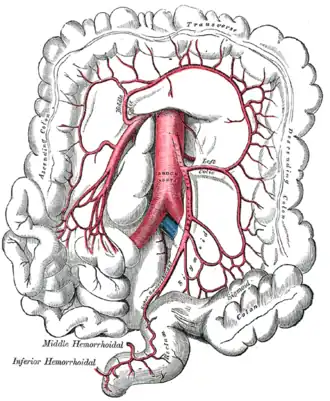

The superior mesenteric artery and its branches. (Middle colic visible at center top.) | |

The middle colic artery is an artery of the abdomen; a branch of the superior mesenteric artery distributed to parts of the ascending and transverse colon. It usually divides into two terminal branches - a left one and a right one - which go on to form anastomoses with the left colic artery, and right colic artery (respectively), thus participating in the formation of the marginal artery of the colon.

The middle colic artery supplies the superior/distal part of the ascending colon and right/proximal two-thirds of the transverse colon.[1]

The middle colic artery is a branch of the superior mesenteric artery, branching off from its right aspect. Its origin is situated just inferior the neck of the pancreas. It may share a common origin with the right colic artery.[2]

The middle colic artery passes anterosuperiorly between the layers of the transverse mesocolon just right of the midline before dividing into left and right terminal branches.[2]

The anastomotic arches formed by the left and right branches of the middle colic artery are about two fingers' breadth from the transverse colon, to which they distribute branches.[3]

The sequence of anastomoses of the branches of the middle colic artery constitutes part of the marginal artery of the colon.[1]

The left branch anastomoses with a branch of the left colic artery (in turn a branch of the inferior mesenteric artery[4]) near the left colic flexure,[2] forming the arc of Riolan.[4]

The right branch anastomoses with the ascending branch of the right colic artery.[2]